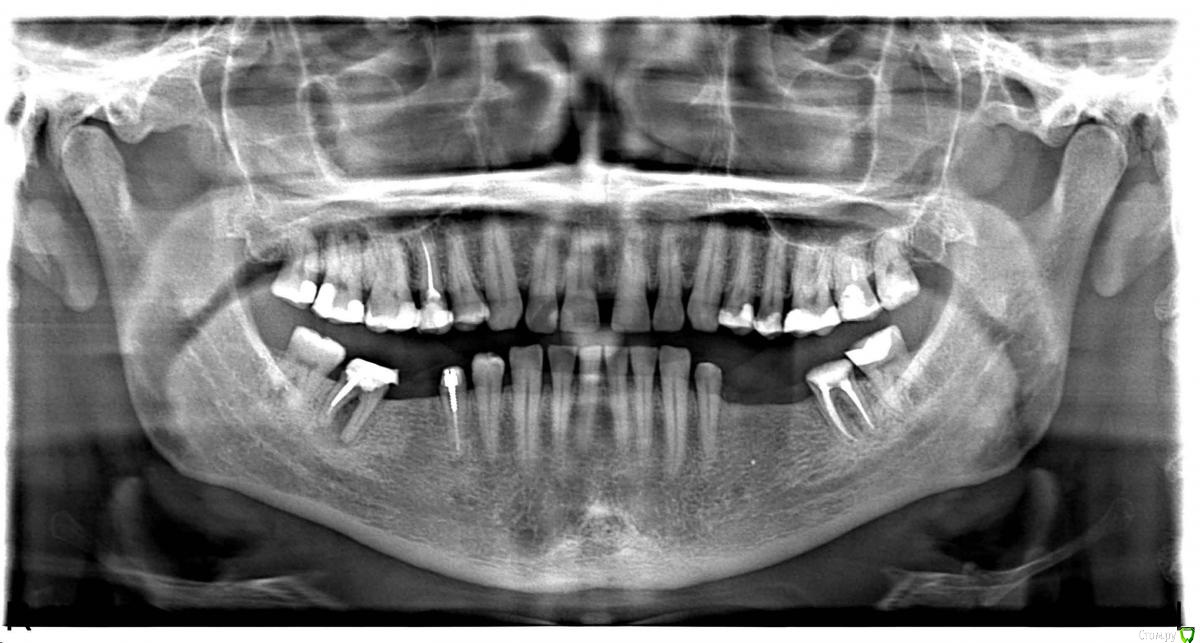

Некий Опубликовано 6 марта, 2017 Поделиться Опубликовано 6 марта, 2017 (изменено) Добрый день! 30.11.2016 - пришлось удалить 47 зуб на фоне воспаления.Удаление быстрое, но производилось не вверх, т.к. штифтованная конструкция развалилась, а в бок.Дня через 4 вышел синяк и немного побаливало.Доктор сказал, что заживление идет штатно.Но так и не заживало окончательно до 06.01.17.В это посещение был удален секвестр костный.После этого в течении недели все заросло.Но оказалось не совсем, т.к. 14.02.17 обнаружил, что острый край (вероятно, сломанной лунки) прорвал десну.С тех пор уже трижды проводили кюретаж поврежденного участка с шлифованием кости. Первый раз ничего не назначая, второй - метрогил дента, третий- солкосерил.Прошла неделя с последнего лечения. Результат не радует Что предпринять в данной ситуации? Заранее спасибо. Изменено 6 марта, 2017 пользователем Некий Ссылка на комментарий